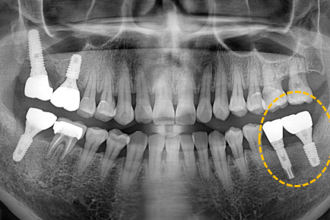

임플란트